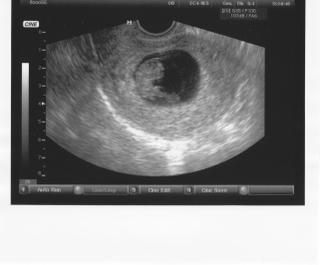

8+1tt x-)

Mame 2,3 cm, srdiecko a vsetko je v poriadku, 2.2. ideme na poradnu a dostaneme aj knizku :-) Dakujeme za drzanie palcov x-)